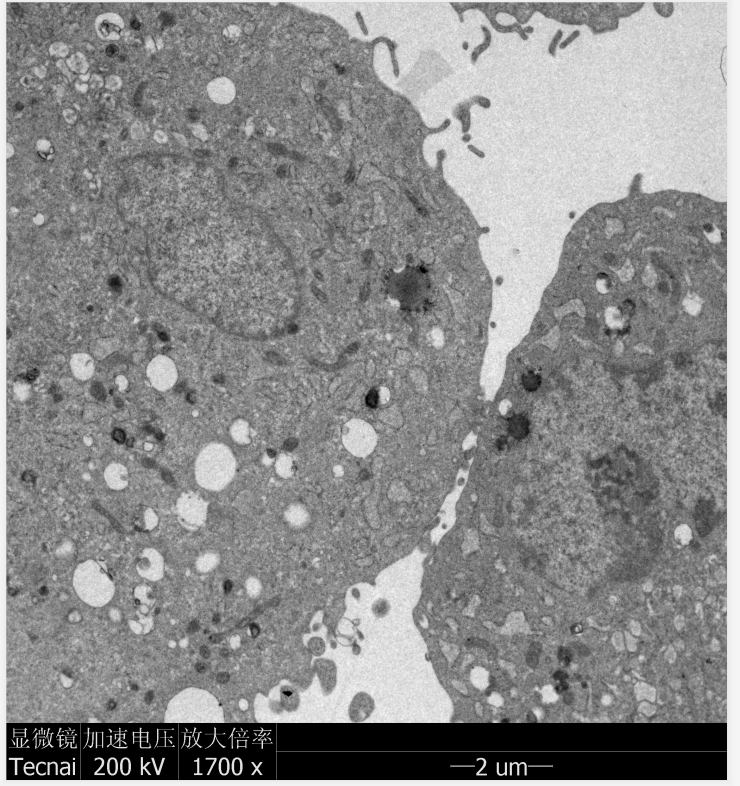

结果展示